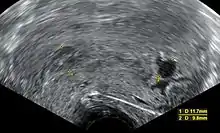

Transvaginal ultrasonography, with some products of conception in the cervix (to the left in the image) and remnants of a gestational sac by the fundus (to the right in the image), indicating an incomplete miscarriage

An incomplete miscarriage occurs when some products of conception have been passed, but some remain inside the uterus.[100] However, an increased distance between the uterine walls on transvaginal ultrasonography may also simply be an increased endometrial thickness and/or a polyp. The use of a Doppler ultrasound may be better in confirming the presence of significant retained products of conception in the uterine cavity.[101] In cases of uncertainty, ectopic pregnancy must be excluded using techniques like serial beta-hCG measurements.[101]